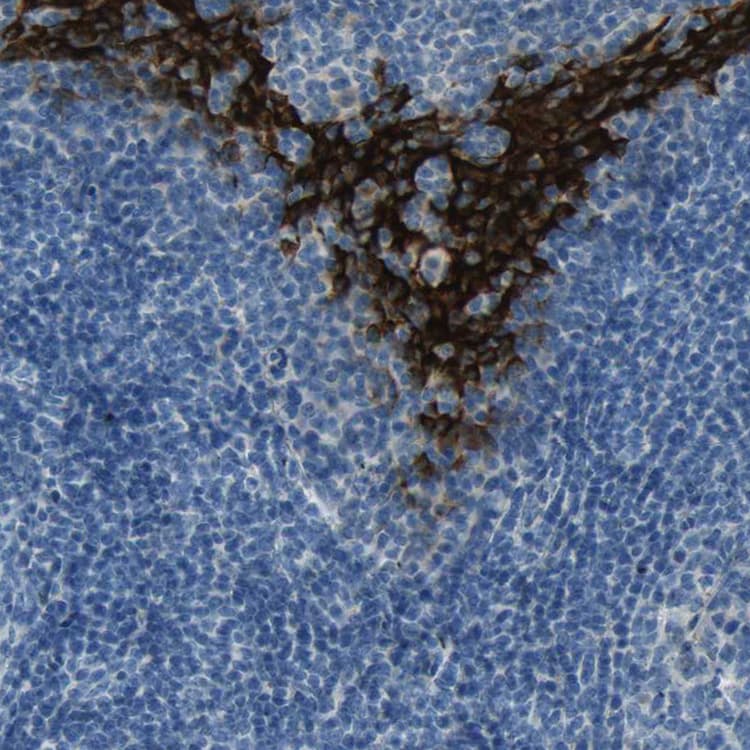

Rabbit Polyclonal SPINK5/LEKTI antibody. Suitable for IHC-P, ICC/IF and reacts with Human samples. Immunogen corresponding to Recombinant Fragment Protein within Human Serine protease inhibitor Kazal-type 5 aa 150-300.